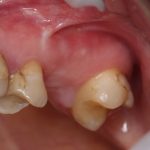

Вот клиническая картина через 4 месяца после ранее проведенной имплантации с остеопластикой:

Как видишь, коллеги из недалекой дружественной страны не осилили снятие швов. Мне это не нравится, хотя и объясняет, почему люди готовы ехать за тыщи километров ради 20-минутной операции удаления зуба мудрости.

Ну хорошо. Швы сняли. Делаем разрез. Обрати внимание, что после всех проведенных операций у нас остается очень небольшой по ширине слой жевательной слизистой оболочки: